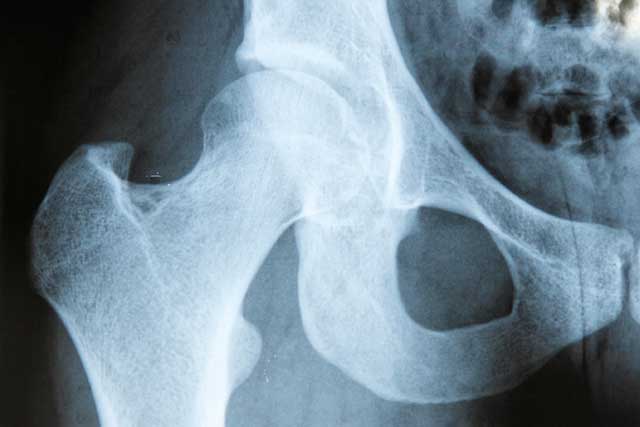

Hip and Knee Service

Problems affecting the hips or knees, such as osteoarthritis, cause significant pain and loss of function to a large number of people. The good news is that we have the ability to help.

Our Hip and Knee Service is dedicated to the diagnosis, investigation and treatment of all types of hip and knee problems deriving from: